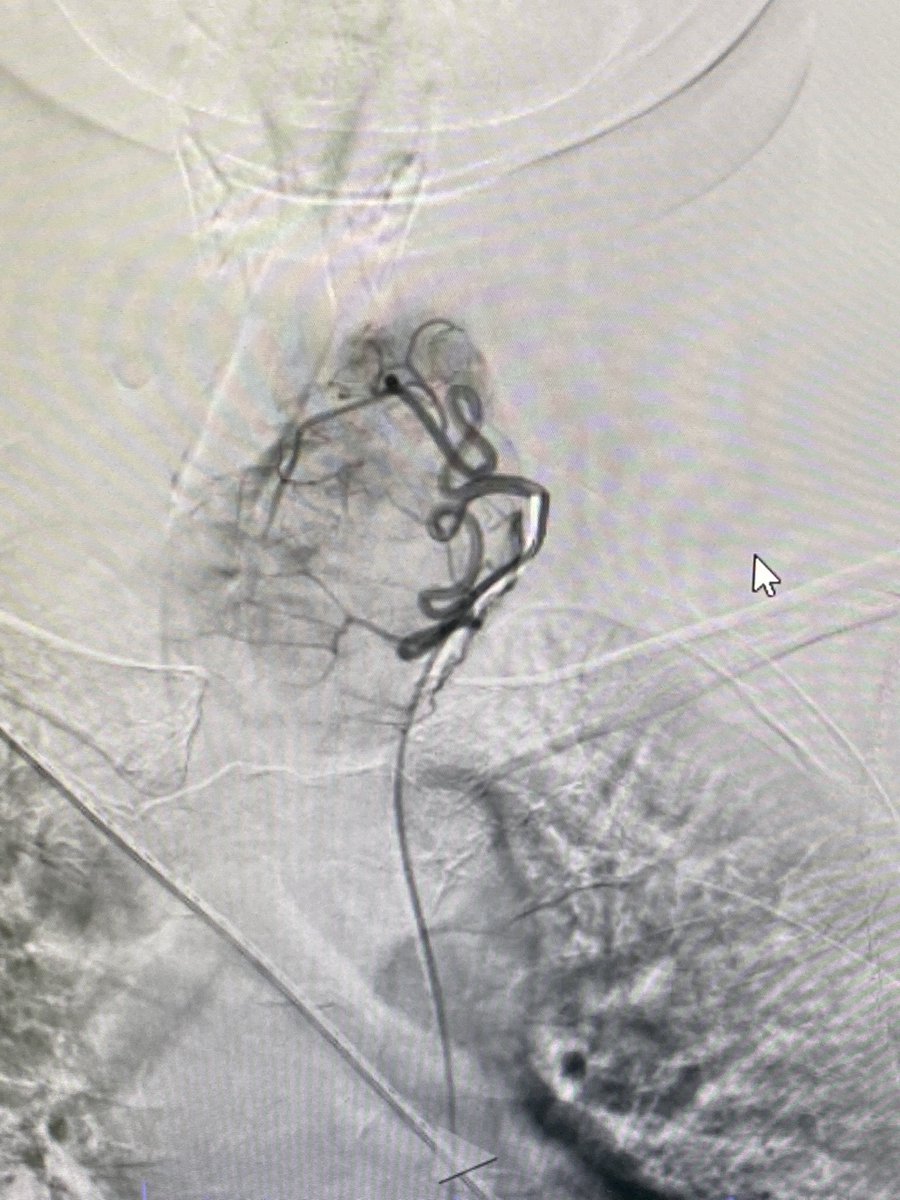

Two weeks ago, a 54-year-old patient recovering from open-heart surgery (CABG) suffered a major stroke. • Symptoms: Sudden inability to speak + right-side paralysis. • Action: Immediate Mechanical Thrombectomy to remove the brain clot.

Manish Kumar Yadav tweet mediaManish Kumar Yadav tweet mediaManish Kumar Yadav tweet mediaManish Kumar Yadav tweet media